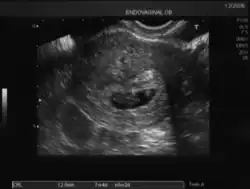

Ecografía de 7 semanas -

Los signos positivos de certeza de un embarazo consisten en poder demostrar sin error la presencia de estructuras embrionarias mediante ultrasonido y otras imágenes radiológicas.

En cualquier momento del embarazo, en especial en presencia de un feto maduro en la segunda mitad del embarazo, es posible demostrar por ecografía transabdominal bidimensional o tridimensional tanto sus partes anatómicas como el saco vitelino.